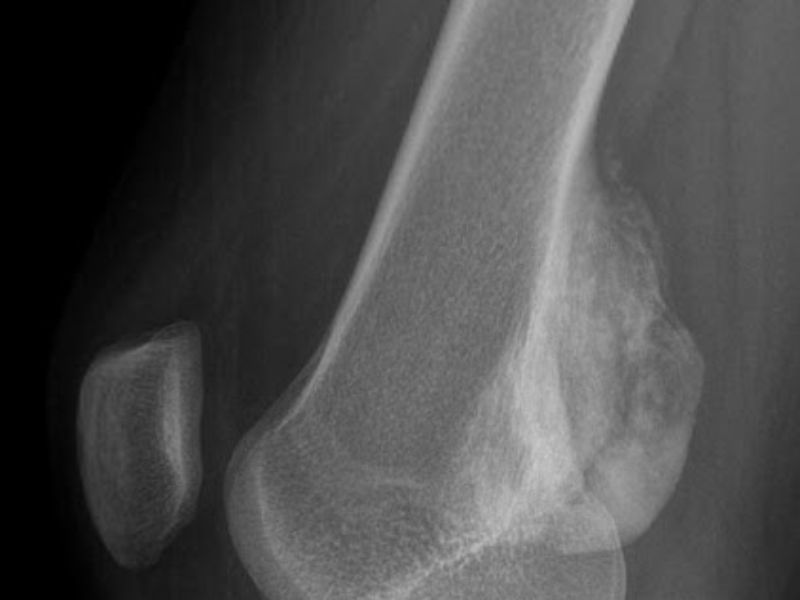

U sụn bao gồm hai dạng u nội sụn (phổ biến) và u nguyên bào sụn hiếm gặp. U nội sụn thường không gây triệu chứng nhưng khối u lớn có thể dẫn đến đau hoặc sưng. U nguyên bào sụn có thể gây đau lan vào khớp và hạn chế vận động, thường có biểu hiện là đường viền calci hóa trong khối u khi xem chẩn đoán hình ảnh.

- Chụp X-quang: Là phương pháp chẩn đoán hình ảnh đầu tiên và phổ biến nhất để phát hiện bất thường trong cấu trúc xương, giúp xác định vị trí khối u, hình dạng, mật độ và mức độ ảnh hưởng đến mô xương xung quanh. Hình ảnh X-quang có thể cho thấy các dấu hiệu như vùng mất xương (tiêu xương) hoặc tạo xương bất thường.